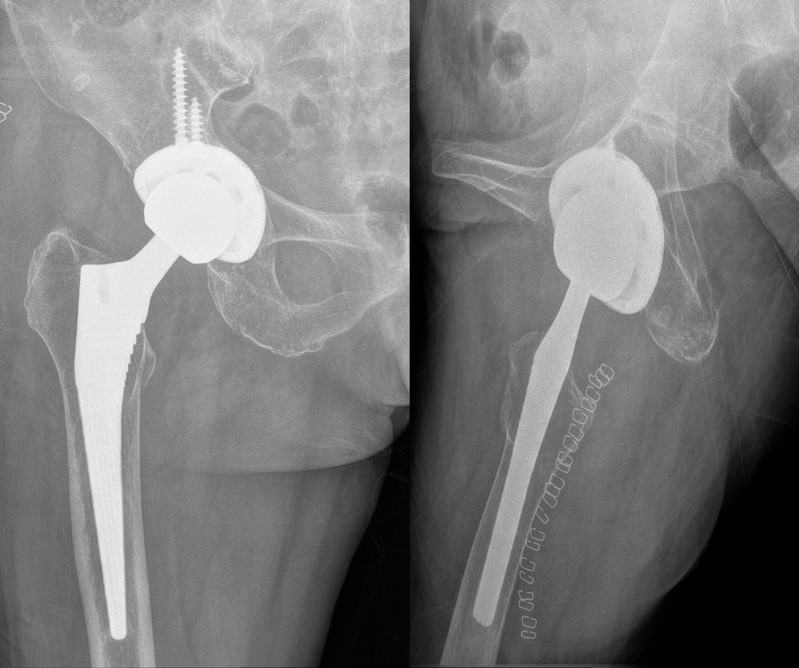

患者张女士现年71岁,14年前因右股骨颈骨折在外院接受了全髋关节置换术,术后即感右髋部疼痛,下地行走后更为明显,且右下肢较对侧变长,询问当时的手术医生后被告知类似情况需要一段时间的恢复。然而,在经过长达数年的恢复后,疼痛不但没缓解,反而加重了。2024年初,张女士右髋部疼痛进一步加重,跛行明显,甚至影响睡眠,只能靠药物勉强维持。为了解决困扰自己多年的顽疾,张女士来到了苏大附四院骨科门诊,王亮副主任医师经过仔细的询问病史、体格检查以及影像学资料研读,判断张女士髋部疼痛的主要原因是髋臼假体外展角度太大(接近60°)、前倾角过小,假体颈过长造成双下肢不等长。要解决这些问题,张女士必须接受髋关节假体翻修手术。

术前右髋关节正侧位片,提示髋臼假体外展角、前倾角异常